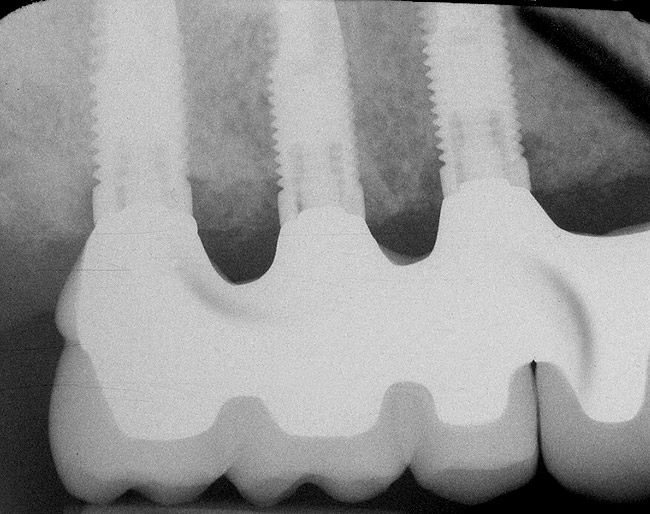

In overdenture therapy, prosthetic design can be divided into two groups: stress-broken and rigid. Stress-broken prostheses require fewer implants, with attention to biomechanical design features to allow for rotation (stress-breaking) of the prostheses around the implant locations. These prostheses are essentially tissue-supported and implant-retained. They replace the adhesive/glue, providing needed retention, comfort, and support. An example would include two implants in site Nos. 23 and 26, with either solitary anchor systems (ball or stud attachments) or a splinted bar-overdenture design (Figure 9 through Figure 11). Masticatory function is improved and patient satisfaction increased. Rigid prostheses require multiple implants, with the forces being transferred from the supra-infrastructure directly to the implants. These prostheses are implant-supported and implant-retained. The design can be removable or fixed (Figure 12 through Figure 16), depending on patient- and operator-mediated preferences.24-27 Within the fixed group of prostheses, materials used may vary from acrylic-fused-to-metal, porcelain-fused-to-metal, or all-ceramic. The cost of these material choices varies significantly, with acrylic options providing the most affordable, entry-level approach for the patient.14